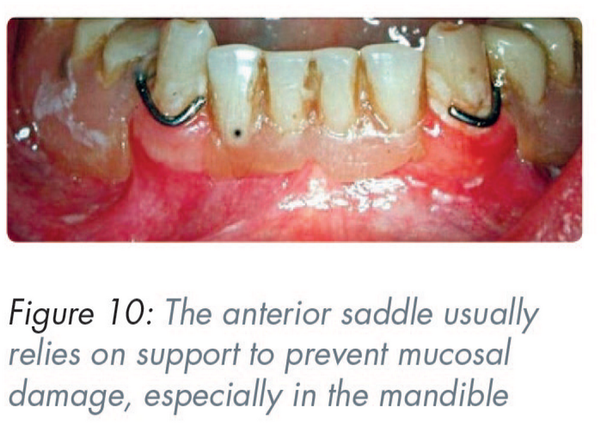

Due to its site, the anterior saddle, particularly in the mandible, often depends on support to prevent the underlying mucosa from damage (Figure 10). When planning a design, the following can be used as solutions: